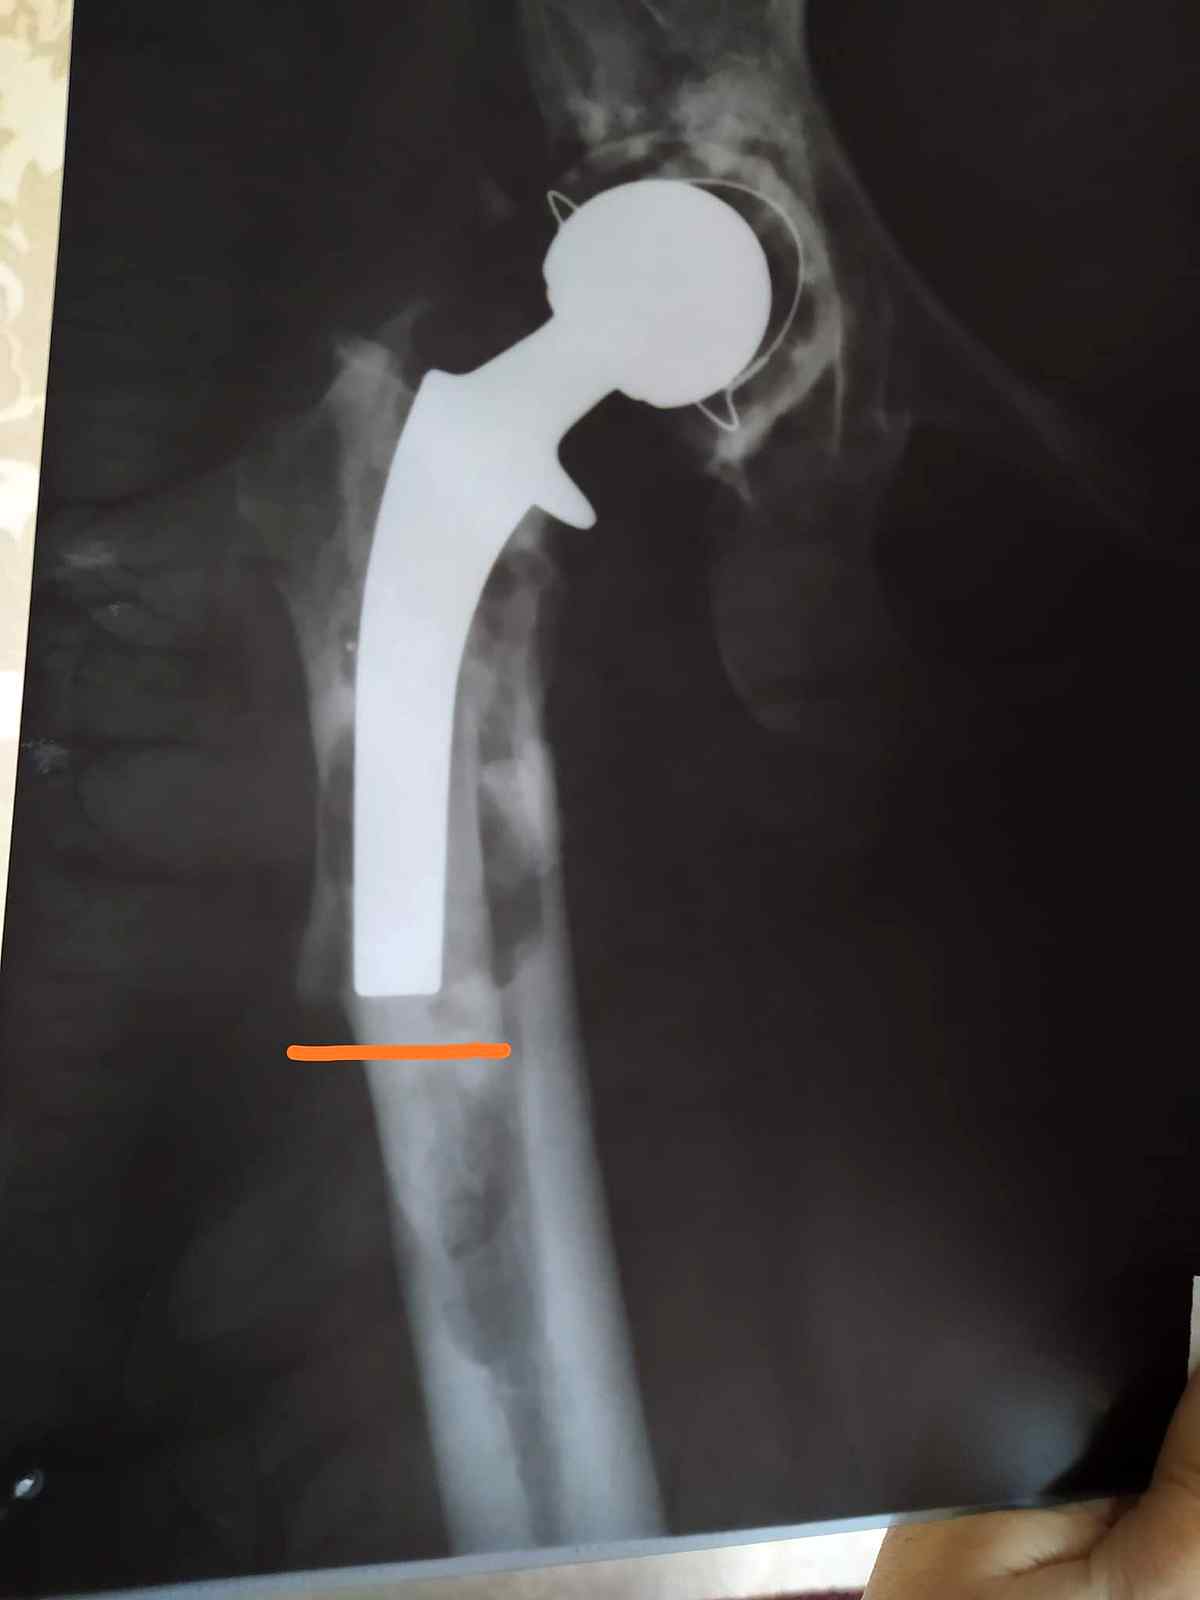

Вінничанка терміново потребує грошової допомоги на заміну ендопротеза тазостегнового суглоба. У Тетяни Ігнатьєвої закритий перелом правої стегнової кістки, нестабільність тазового ендопротезу правого кульшового суглобу. 14 років тому їй робили цю операцію, цього року потрібно знову. Сьогодні вона немає змоги її оплатити, повідомляє Vlasno.info.

17 грудня Тетяна Ігнатьєва зробила рентген. З отриманих знімків лікарі сказали, що необхідно робити терміново операцію, яка коштує від 100 тисяч гривень. Ця сума є великою для родини жінки.

– Мама зараз вдома, ходить на милицях. Якщо мама зараз буде ходити без милиць, то повністю переламає ногу. Тому що крім заміни протеза, їй необхідно ставити хомут на кістку, щоб зміцнити її. Ендопротез ставится на цементі, цей цемент зруйнував і зламав її кістку. Тому операція буде складною, – каже Саша.